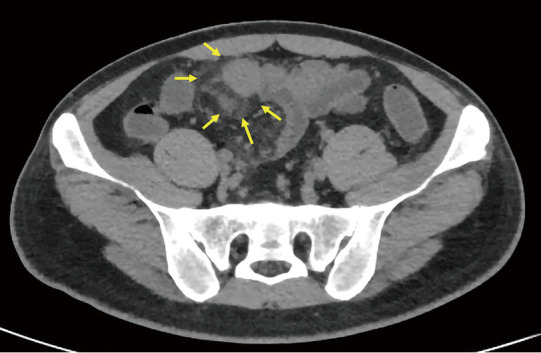

Background: Creeping fat (CF), a characteristic structure of Crohn's disease (CD), is closely associated with surgery and prognosis but lacks a unified imaging assessment standard, and endoscopic and serological indicators have limitations in evaluating extra-intestinal lesions. The study aimed to explore the correlation between computed tomography (CT) value distribution changes of mesenteric-surrounding fat in CD and disease activity.

Methods: In this study, we retrospectively analyzed CT enterography (CTE) images from 47 pathologically confirmed CD patients and 25 randomly selected controls with suspected inflammatory bowel disease (IBD). Quantitative measurements were obtained for mesenteric adipose tissue density (mean of CT values) along key anatomical landmarks including the mesenteric root, superior mesenteric artery, inferior mesenteric artery, perilesional regions, intestinal stricture, and adjacent branching vascular spaces. Other evaluated parameters included bowel wall thickness, CT attenuation, enhancement patterns, and CF grading. Qualitative evaluations were made by comparing with endoscopic, serological, and histopathological results and simplified CD activity index (CDAI) scores. A patient with concurrent anal fistula underwent magnetic resonance imaging (MRI) examination to compare its detection efficiency of fistula with that of CT examination.

Results: Significant inter-group differences were found in non-contrast mesenteric fat attenuation, mean ΔCT (difference in Hounsfield units between contrast-enhanced CT and non-contrast CT scans) enhancement, bowel wall thickening, mucosal enhancement, CF grading, intestinal stricture, and serological parameters (P<0.05). The moderate-to-severe activity group had the highest mesenteric fat density in the venous phase [mean ΔCT >20 Hounsfield units (HU), P<0.05], especially around lesions. There was a positive correlation between mesenteric fat CT values and images of diseased bowel segments. The mean value of the venous phase ΔCT of the lesion and the mean of the intestinal wall venous phase ΔCT value and intestinal wall stratification were positively correlated (>0.6, P<0.05). ROC analysis showed that the venous-phase ΔCT of perilesional adipose tissue had excellent diagnostic performance [area under the curve (AUC) =0.964] for moderate-to-severe activity CD, with 95.8% sensitivity and 87.5% specificity. The diagnostic efficacy of the venous phase in the vascular space around the lesion ranked second (AUC =0.943). MRI showed superior detection of the anal fistula to that of CT in one patient. Multivariate analysis confirmed it as an independent predictor for moderate-to-severe active CD (P<0.05).

Conclusions: Changes in mesenteric adipose tissue CT values and CF classification can distinguish CD from other IBD, suggesting their utility as another noninvasive diagnostic method for predicting the inflammatory activity of CD and evaluating the scope of surgery.